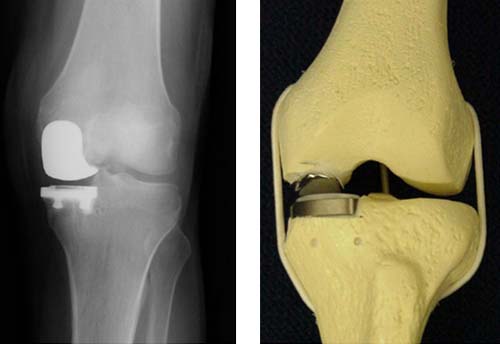

На четвертой стадии заболевания сустав уже практически разрушен. В данном случае проводится хирургическая операция по установлению эндопротеза. Такой протез позволяет пациенту возобновить активную жизнь и избавиться от болевых ощущений.

Самым серьезным осложнением артроза является полное разрушение хряща, в результате чего может полностью утратиться подвижность сустава. Единственным выходом в данном случае будет протезирование.